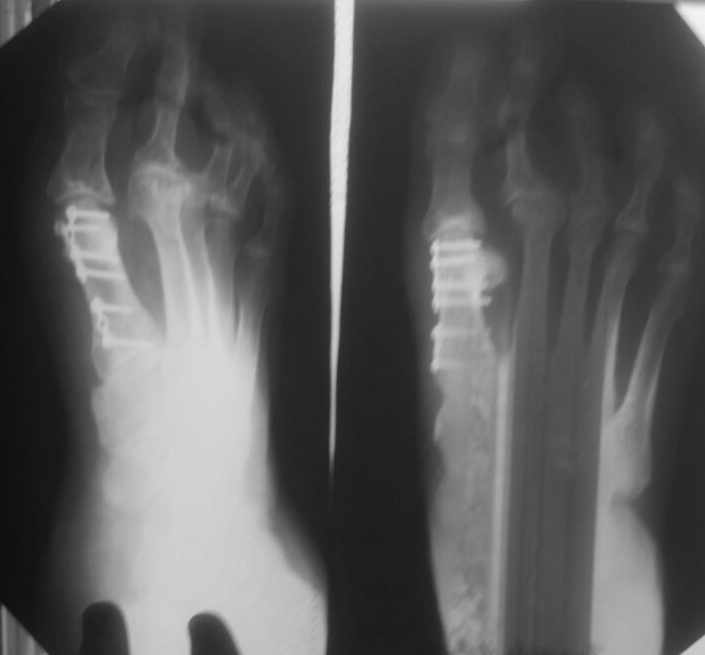

женщина средних лет, оперирована около года назад

Неутолимое желание поставить больше железок. 6 или 7 винтов и 2 пластины на одну плюсневую. Первичных снимков нет, но можно предположить, что 2 остеотомии привели к значительному укорочению М1. В результате - переходная метатарзалгия. Была или нет до операции деформация центральных пальцев тоже не знаем. Сейчас видны молоткообразная деформация второго пальца с преобладанием его длины над первым, перекрест второго и третьего пальцев. Если выпрямить второй - станет еще длиннее. А выпрямить может помешать отклоненный кнутри третий палец - второму некуда улечься. Поэтому нужно думать об остеотомии 2-4 плюсневых для устранения метатарзалгии (фиксированный или нефиксированный Вейль, DMMO - чем владеете), коррекции молоткообразной деформации второго (с его укорочением) и варусной деформации третьего пальца (возможно и четвертого, если будет мешать выпрямить третий). На болезнь Фрайберга не очень похоже. Скорее это подвывих пальца на некачественных снимках имитирует. В любом случае - моделирующая резекция - калечащая сустав операция. Декомпрессии за счет укорочения будет достаточно. Если есть возможность оперировать чрескожно - самый простой и беспроигрышный вариант.